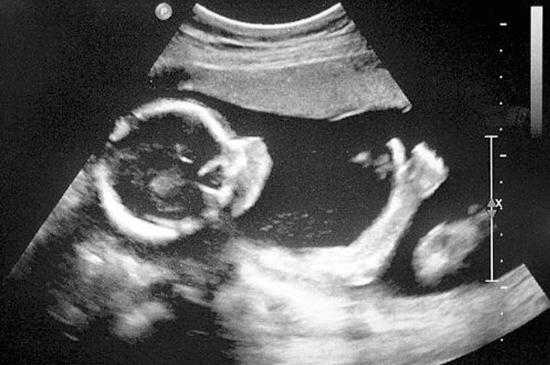

b.四肢

c.心脏

d.重点来啦,男宝和女宝,别说你不会看!